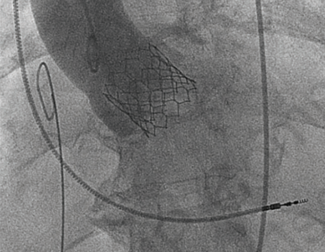

Sapien 3 Valve

TAVR Valve Deployment

06/11/2023

Gilbert H.L. Tang, MD, MSc, MBA

Gilbert Tang, MD, MSc, MBA, Surgical Director, Structural Heart Program, Mount Sinai Health System; Professor, Cardiovascular Surgery, Icahn School of Medicine at Mount Sinai, New York, New York.